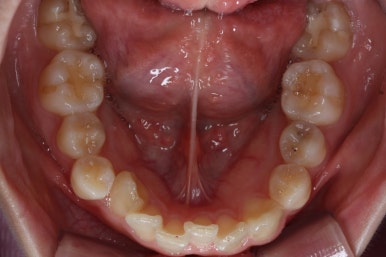

아랫니에도 이제 장치를 붙였습니다.

과개교합인 채로 아랫니에도 장치를 붙이게 되면 아랫니 장치가 깨물려서 다 떨어지거나 부서지기 쉽습니다. 따라서 바이트터보는 굉장한 역할을 하게 됩니다.

눈으로 보기에는 과개교합이 개선이 된 것처럼 보이지만 아직은 아닙니다. 바이트터보가 남아있는 채로도 어금니가 맞물려야 진짜로 개선된 것이죠.